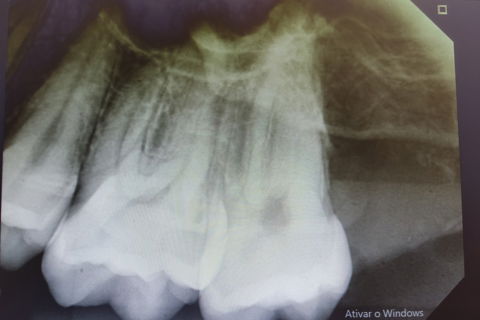

Raio-x Panorâmico

Paciente B. F. L. , compareceu ao meu consultório relatando dores na região dos dentes do siso apesar de estarem inclusos, paciente relatava bastante "pressão" na região e nos dentes. Outra queixa era a ausência do segundo molar inferior do lado esquerdo. Foi realizado consulta, anamnese, paciente "ASA1" solicitação de raio-x panorâmico. Após avaliação do raio-x panorâmico observei que o paciente possuía os dentes 18, 28, ,37 38, 48 inclusos/impactados. Os terceiros molares apresentavam-se mesio-angulados quase horizontais. Após planejamento cauteloso, foi realizado a remoção dos 5 dentes inclusos em uma única etapa cirúrgica. Observem nas imagens que a incisão "relaxante" na região cirúrgica dos dentes 37 e 38, foi realizada na mesial do dente 35 (isso para que se haja um bom afastamento do retalho para melhor visualização e acesso). Foi passado as medicações pós cirúrgicas para o paciente e nesse caso o corticóide foi receitado, para evitar edemas devido grande acesso cirúrgico; além do antibiótico, antiinflamatório e analgésico (gosto muito de receitar o toragesic).